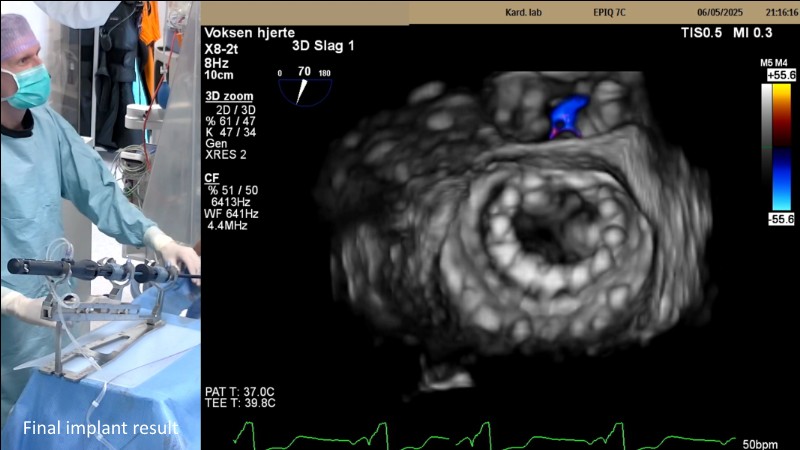

This EuroPCR 2025 session highlights the evolving role of transcatheter mitral valve replacement, focusing on the clinical potential of mitral regurgitation elimination. Get an overview of the current status of the Intrepid TMVR programme, learn about the transition to the 29Fr transfemoral system, and explore how patient screening—especially in the presence of mitral annular calcification—impacts procedural planning. Real-world case reviews from the APOLLO-EU trial offer practical insights into how this next-generation system is being applied in Europe today.